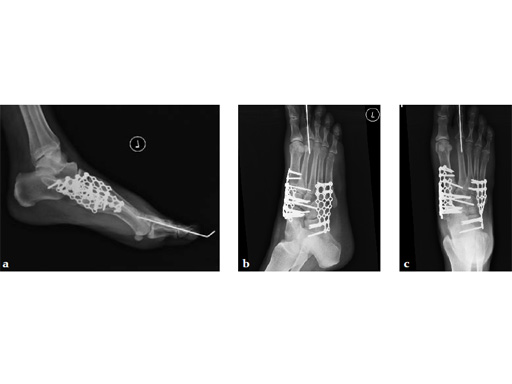

Case 8: VA -locking X-plate

A 38-year-old man fell from a 7-foot height while at work. The patient was seen at an urgent care facility and diagnosed with an ankle sprain. He was placed in a stirrup brace and instructed to bear weight as tolerated.

Case provided by Michael Castro, Scottsdale, Arizona

After 4 months the patient presented for a second opinion. His complaint was pain to the lateral column and subtalar joint. The preoperative lateral x-ray is notable for a malunited talar neck fracture with subluxation of the subtalar joint. The disproportion of the medial and lateral columns and a cavovarus position of the foot are seen on both the AP and lateral views. The degenerative changes at both the talonavicular and subtalar joints are significant.

The patient was treated with arthrodesis of the talonavicular and subtalar joints. The compression/ distraction device was used to restore the length of the medial column. The articular surface of the subtalar joint was prepared arthroscopically. The talonavicular joint was debrided then packed with a tricalcium matrix. Length was maintained using a locking X-plate. The subtalar joint was then fixed with a 6.5 mm headless compression screw.

The patient returned to work 3 months after surgery. He wears an ankle brace when on uneven surfaces. His lateral column and subtalar pain have resolved.